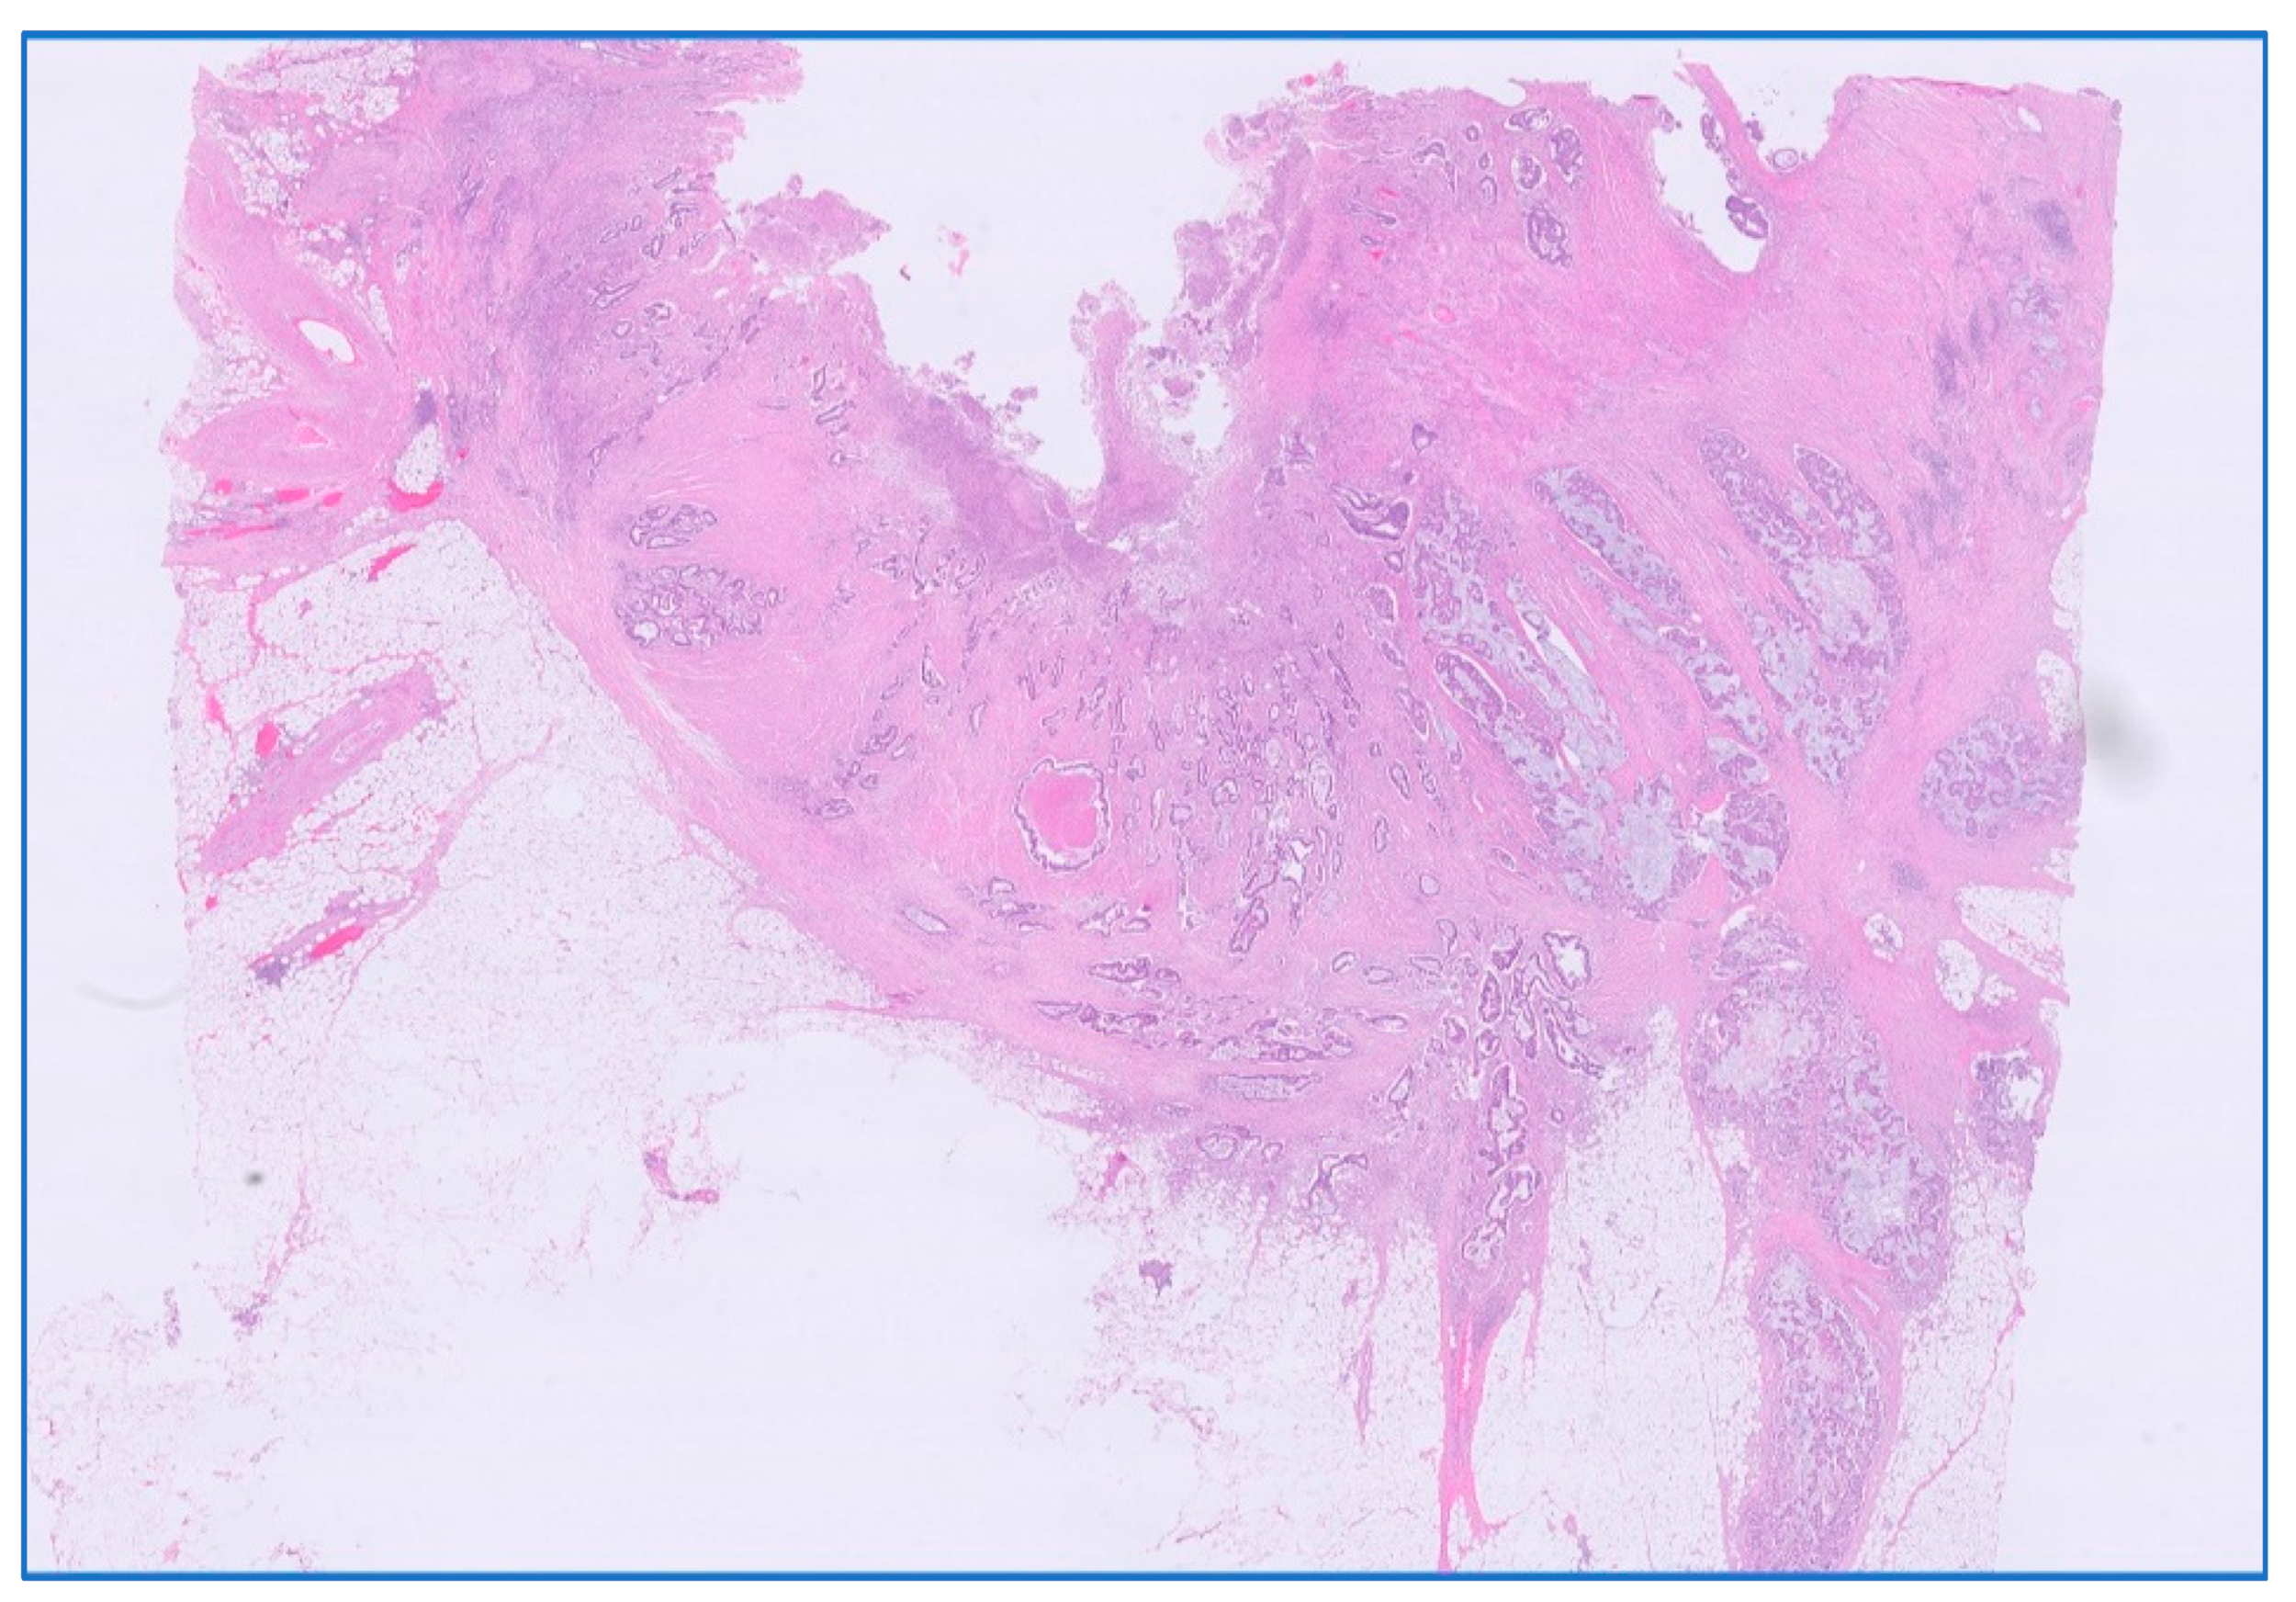

Figure 6.

Persistent rectal adenocarcinoma after neoadjuvant radiochemotherapy; ypT3 with invasion in subserosal adipose tissue. HE stain × 0.5 magnification.